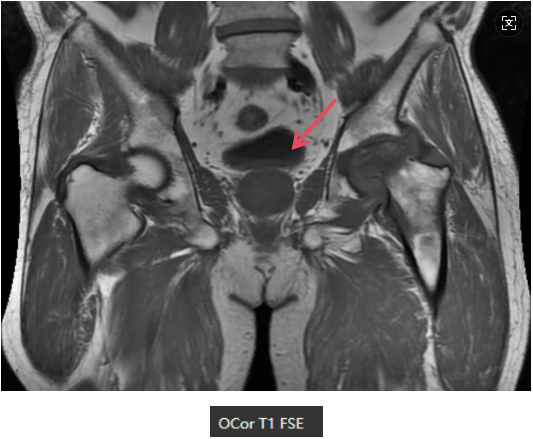

MR表现

左侧股骨头变扁,局部塌陷,骨质内见线状T1WI低信号,髋臼及股骨近端骨松质见片状T1WI低、T2WI压脂高信号,DWI高信号,周围滑膜增厚,邻近软组织肿胀,PD压脂信号增高,关节腔少量积液。